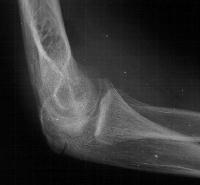

Five years later, he has limited motion (E/F 35/100) and painful clicking with elbow flexion and extension.

Plain films show humeral osteophytes and posttraumatic changes of the capitellum and radial head.

Treatment options? Do nothing, Open reduction and bone graft, sequestrum excision or radial head excision. In this case, at surgery, the loose articular fragment was too thin to allow reliable fixation, and was simply excised.

Postoperatively, pain is improved, although some clicking persists. Range of motion is marginally improved. Radial head excision remains an option if he has painful problems later.